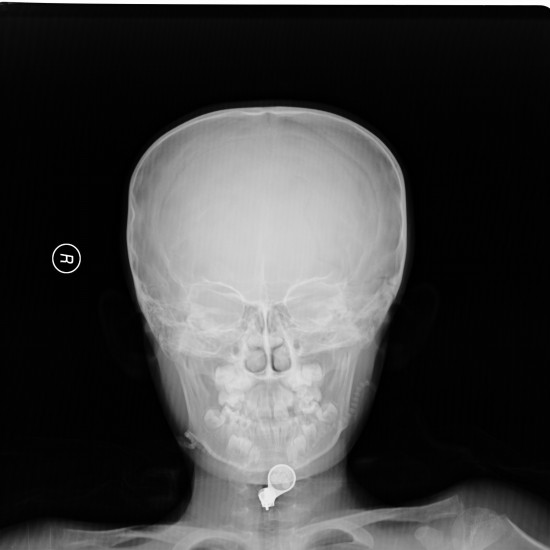

标题: x4344:男,9岁。好久不见的东西了。左枕部外伤一周。 [打印本页]

标题: x4344:男,9岁。好久不见的东西了。左枕部外伤一周。

考虑:硬化型乳突--中耳炎,

上部颈椎可疑畸形,待除外颅底凹陷,建议mri.

侧位不标准,左侧人字缝增宽,有外伤史吗?其他无明显异常。

左侧枕乳缝增宽,提示颅缝分离型骨折。

建议加照汤氏位。

颅骨骨折.

都愿往复杂方面想,很简单,左枕部线形骨折,我仅这么认为。

支持左枕部线形骨折。

枕骨骨折、左侧顶乳缝分离。

支持 左侧颞枕部颅骨线形骨折。建议:ct扫描检查了解颅内情况。